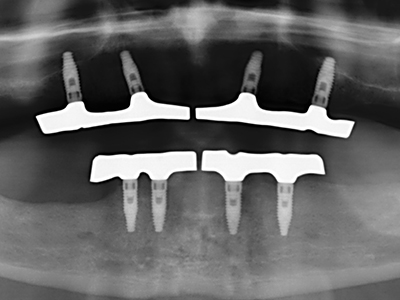

When surgical procedures are performed on bone in the immediate vicinity of sensitive structures such as blood vessels or nerves, rotary instruments pose a significant risk of iatrogenic injury. Piezoelectric devices can be helpful for preparation of bone covers and removal of hard tissue close to nerves, particularly for exposure of nerves after iatrogenic injury but also during nerve lateralization for resective and reconstructive procedures or implant placement (Fig. 17-20). Light contact between the piezotip and the nerve does not generally result in damage but proceeding incautiously with saw-like motions or attachments where a residual bone substrate remains may cause temporary or even permanent nerve damage. However, the risk of damage is considered to be substantially lower than when using saws or milling instruments (Pereira, Gealh et al. 2014).